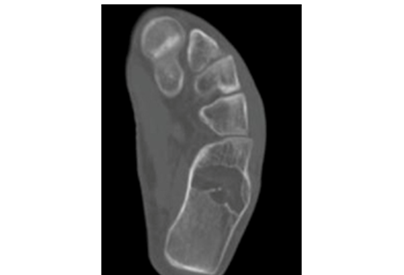

Intraosseous lipomas are diagnosed with plain radiography and CT scan (Figure 1) (Figure 2A) (Figure 2B). Mainstay of treatment is conservative; however surgery is indicated in severe pain not responding to conservative treatment, impending pathological fracture and malignant transformation (Figure 3). Treatment for these tumors is curettage and bone grafting (Figure 4) with good prognosis.8–10

Figure 4 Post curettage and bone grafting.